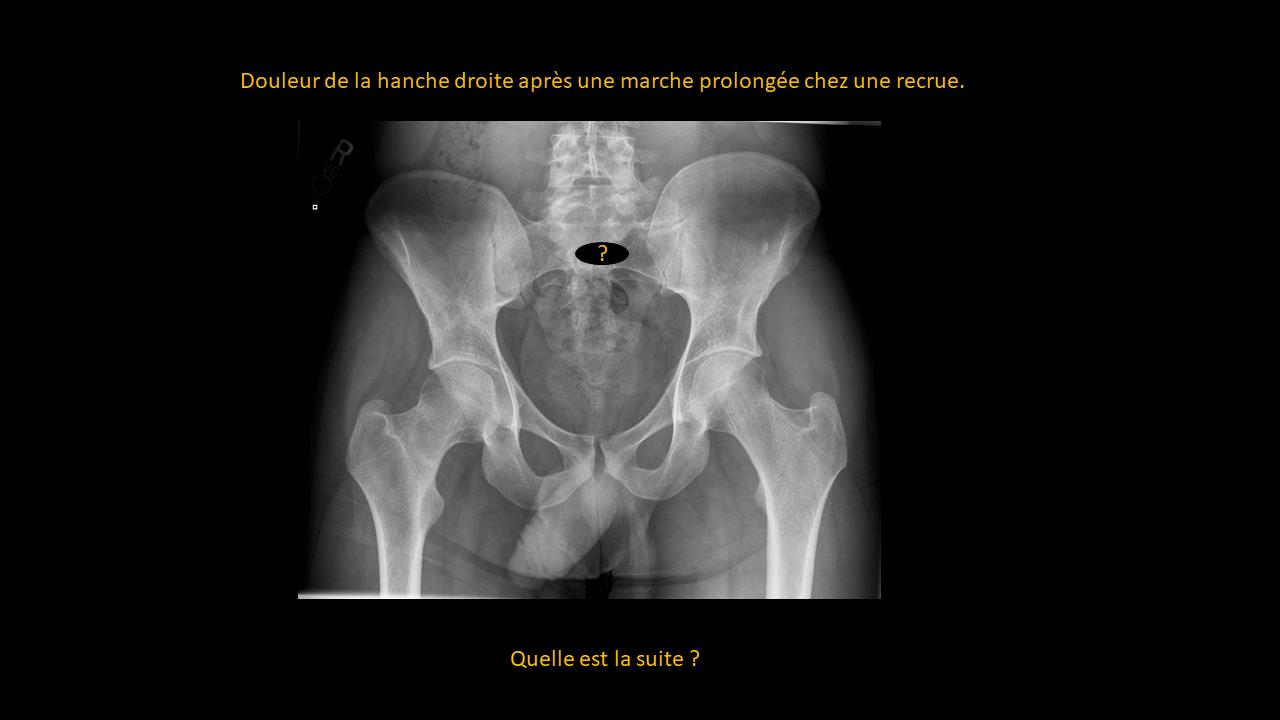

Présentation clinico-radiologique 87

_______ cliquer ici pour la réponse ________